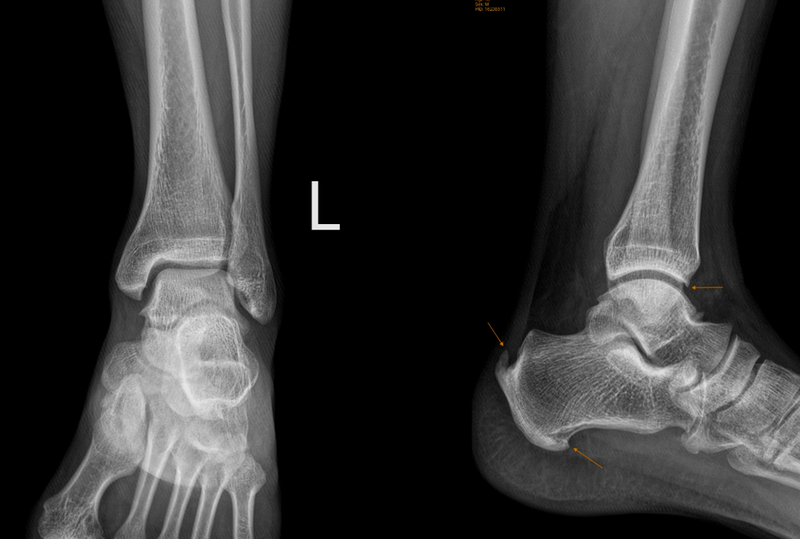

Để xác định triệu chứng đau, bạn nên thăm khám bằng cách ấn lên vùng xương bị tổn thương. Cụ thể, chụp X-quang là phương pháp đầu tiên để giúp chẩn đoán chính xác xương thuyền phụ. Ngoài ra, có thể chụp MRI tiểu khung để có thể đánh giá kỹ lưỡng hơn nếu bị đau và viêm kéo dài.

Để xác định hội chứng xương thuyền phụ, bác sĩ thường dựa vào các biểu hiện và kiểm tra sau đây: